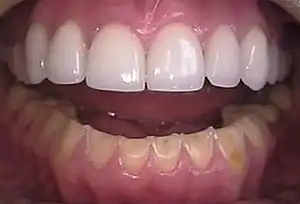

| Loss of enamel (acid erosion) from the inside of the upper front teeth as a result of bulimia | |

- Perimolysis, or severe dental erosion of tooth enamel[17]

People with bulimia are more likely than people without bulimia to have an affective disorder, such as depression or general anxiety disorder. One study found 70% had depression at some time in their lives (as opposed to 26% for adult females in the general population), rising to 88% for all affective disorders combined.[25] Another study by the Royal Children's Hospital in Melbourne on a cohort of 2,000 adolescents similarly found that those meeting at least two of the DSM-IV criteria for bulimia nervosa or anorexia nervosa had a sixfold increase in risk of anxiety and a doubled risk for substance dependency.[26] Some with anorexia nervosa exhibit episodes of bulimic tendencies through purging (either through self-induced vomiting or laxatives) as a way to quickly remove food in their system.[27] There may be an increased risk for diabetes mellitus type 2.[28] Bulimia also has negative effects on a person's teeth due to the acid passed through the mouth from frequent vomiting causing acid erosion, mainly on the posterior dental surface.